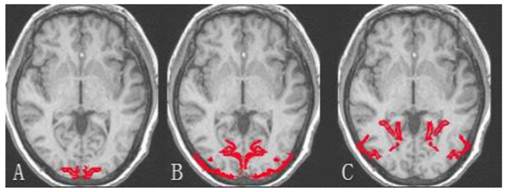

Figure 1

The demarcation of brain occipital lobe. A: Striate cortex; B and C: Extrastriate cortex.